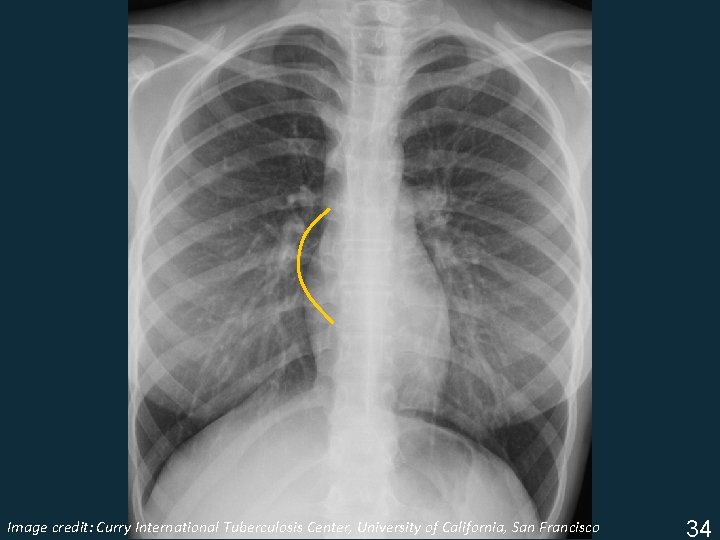

Lymphadenopathy (LAN) § Non-specific terms: • Mediastinal widening • Hilar prominence § Specific patterns: • Particular station enlargement (location) Important to know what “normal” should look like in order to recognize “abnormal” ISTC TB Training Modules 2009 33

Image Tuberculosis Center, University of California, San Francisco ISTC TBcredit: Training Curry Modules. International 2009 34

Lymphadenopathy § Infrahilar window (right hilar and/or subcarinal) § Left hilar § Subcarinal Image Tuberculosis Center, University of California, San Francisco ISTC TBcredit: Training Curry Modules. International 2009 35